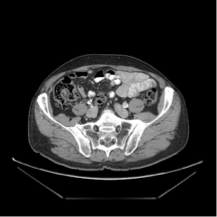

4. RIFE를 이용한 Image Interpolation(CT 이미지)

http://www.castlemountain.dk/atlas/index.php?page=mulrecon에서 다운로드 하였습니다.(JPEG파일)

http://castlemountain.dk/mulrecon/abdomenBladderCancerCT.zip : 다운로드 주소

입력 이미지로 다음의 이미지를 삽입하였습니다.

출력 결과 위의 두 이미지 사이에 밑의 3이미지가 추가로 생성되었습니다.